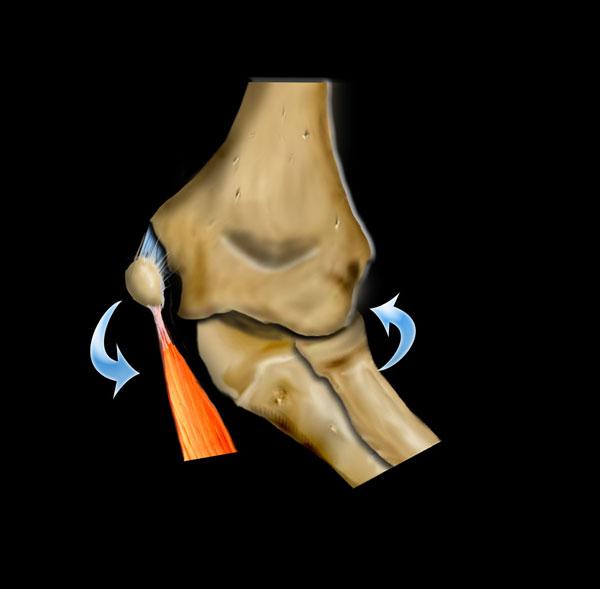

Chấn thương khớp khuỷu tay thường là kết quả của tình trạng duỗi quá mức hoặc vẹo ngoài quá mức do ngã chống tay ra phía trước.

Cuộn qua các hình ảnh ở bên trái để xem cách duỗi quá mức dẫn đến gãy xương trên lồi cầu.

Cơ chế gãy xương quan trọng khác là tình trạng valgus cùi chỏ quá mức.

Khuỷu tay bình thường đã có tư thế valgus sẵn.

Khi trẻ ngã chống tay với cánh tay duỗi thẳng, điều này có thể dẫn đến valgus quá mức.

Ở phía ngoài, điều này có thể dẫn đến trật khớp hoặc gãy xương quay có hoặc không kèm theo tổn thương mỏm khuỷu.

Khi lực tác động nhiều hơn lên xương cánh tay, tình trạng valgus quá mức sẽ dẫn đến gãy lồi cầu ngoài.

Ở phía trong, lực valgus có thể dẫn đến bong lồi cầu trong.

Do tư thế valgus của khuỷu tay bình thường, bong lồi cầu ngoài sẽ ít gặp hơn.